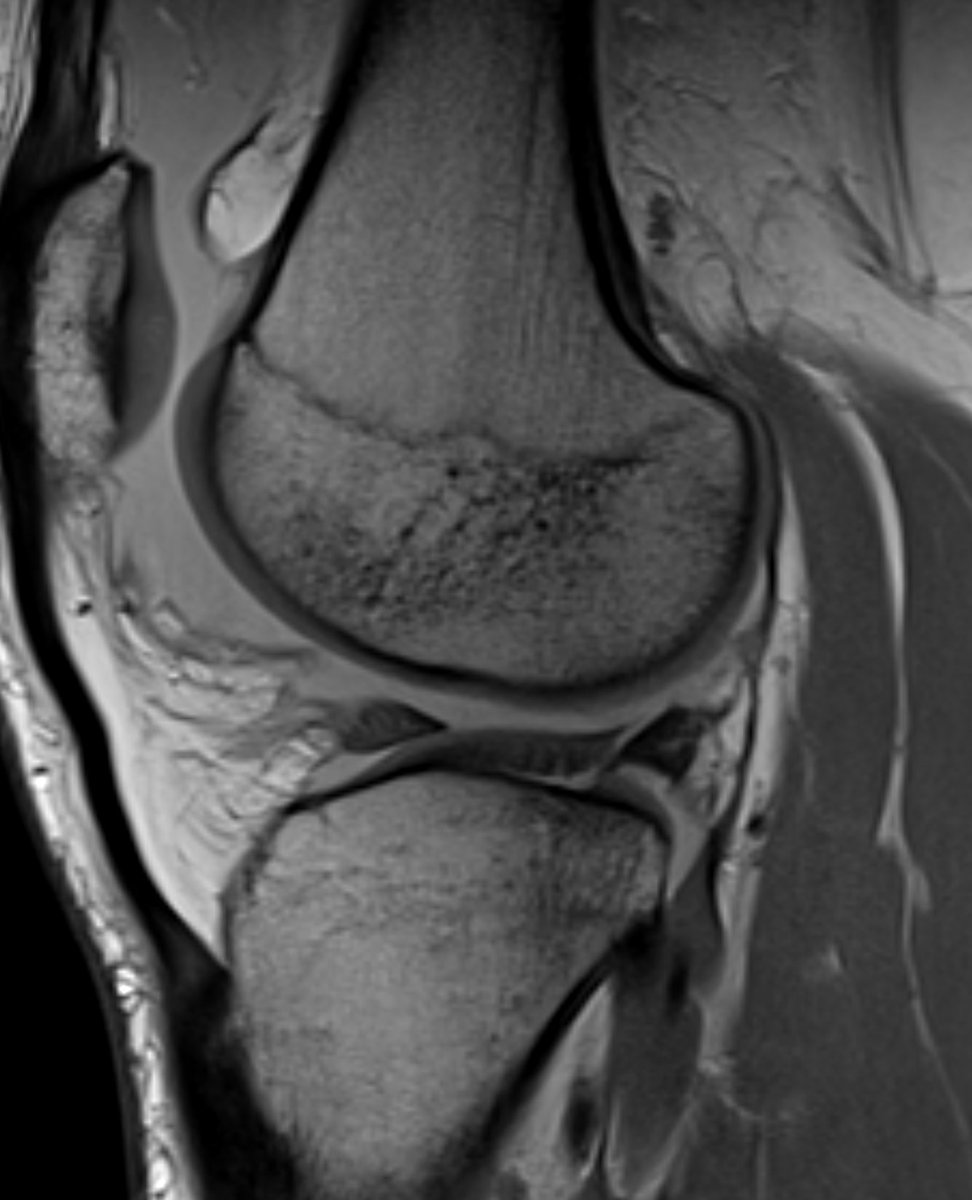

MRI-RADIOGRAPHY CORRELATION: Posterior cruciate ligament tibial avulsion fracture. Difficult x-ray dx if only minimally displaced. On the lateral view, fx projects below the joint line. NYU_MSK Radiology SSR_RWG European Society of Musculoskeletal Radiology OCAD MSK SERME International Skeletal Society | ISS NYU Radiology Residency